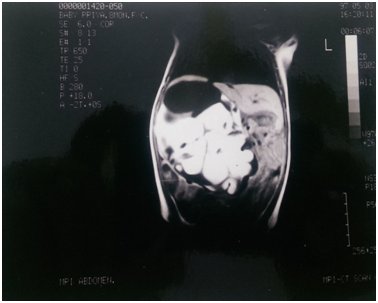

An eight month old male infant weighing 7 kgs was brought with a history of a progressively increasing lump in the right flank of two months duration. There was no associated fever, urinary symptoms or alteration of bowel habits. The child was a full term normal vaginal delivery and developmental milestones were essentially normal. Examination of the abdomen revealed a soft tissue mass approximately 8 x 10 cms in the right hypochondrium causing bulging of the right flank. The mass was ballotable and non-tender and the clinical diagnosis was of a large hydronephrosis. Ultrasound revealed the mass to be a multiseptate, predominantly cystic mass displacing the right kidney posteriorly and inferiorly and was opined to be a cystic neuroblastoma. An IVU confirmed the mass to be superior to the right kidney which was displaced downwards. MRI showed a soft tissue, partially cystic, retroperitoneal mass displacing the liver anteriorly and the kidney downwards (Figure 1) (Figure 2). The right adrenal was not separately identifiable. The mass was filling up the right side of the abdomen and was compressing the IVC in the entire length. Fine needle aspiration cytology from the mass resulted in the aspiration of clear fluid and cytology revealed round cells.

Figure 2 Axial section on the MRI Abdomen showing a soft tissue mass.

The child was subjected to an exploratory laparotomy and the entire mass, 8 x 7 x 5 cms in size and weighing 486 gms was completely excised. The post operative period was uneventful. Histopathological examination revealed the mass to be a benign retroperitoneal teratoma predominantly containing mature, well differentiated brain tissue in addition to adipose tissue, muscle, gastro-intestinal tissue and stratified squamous epithelium (Figure 3). No immature neural tissue was seen. The interesting thing about this case is that, in retrospect, the mass seen on the MRI looks very similar to a brain (Figure 1). The child has been under follow up for eight years and is doing well.